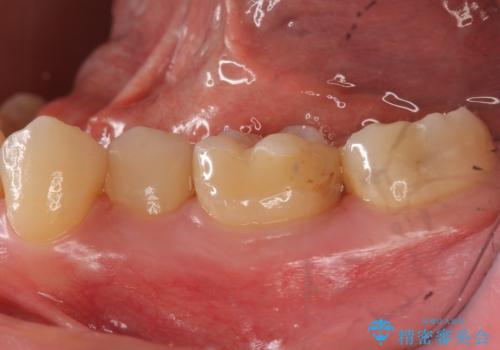

奥歯の詰め物の変色 セラミッククラウンでのやり替え